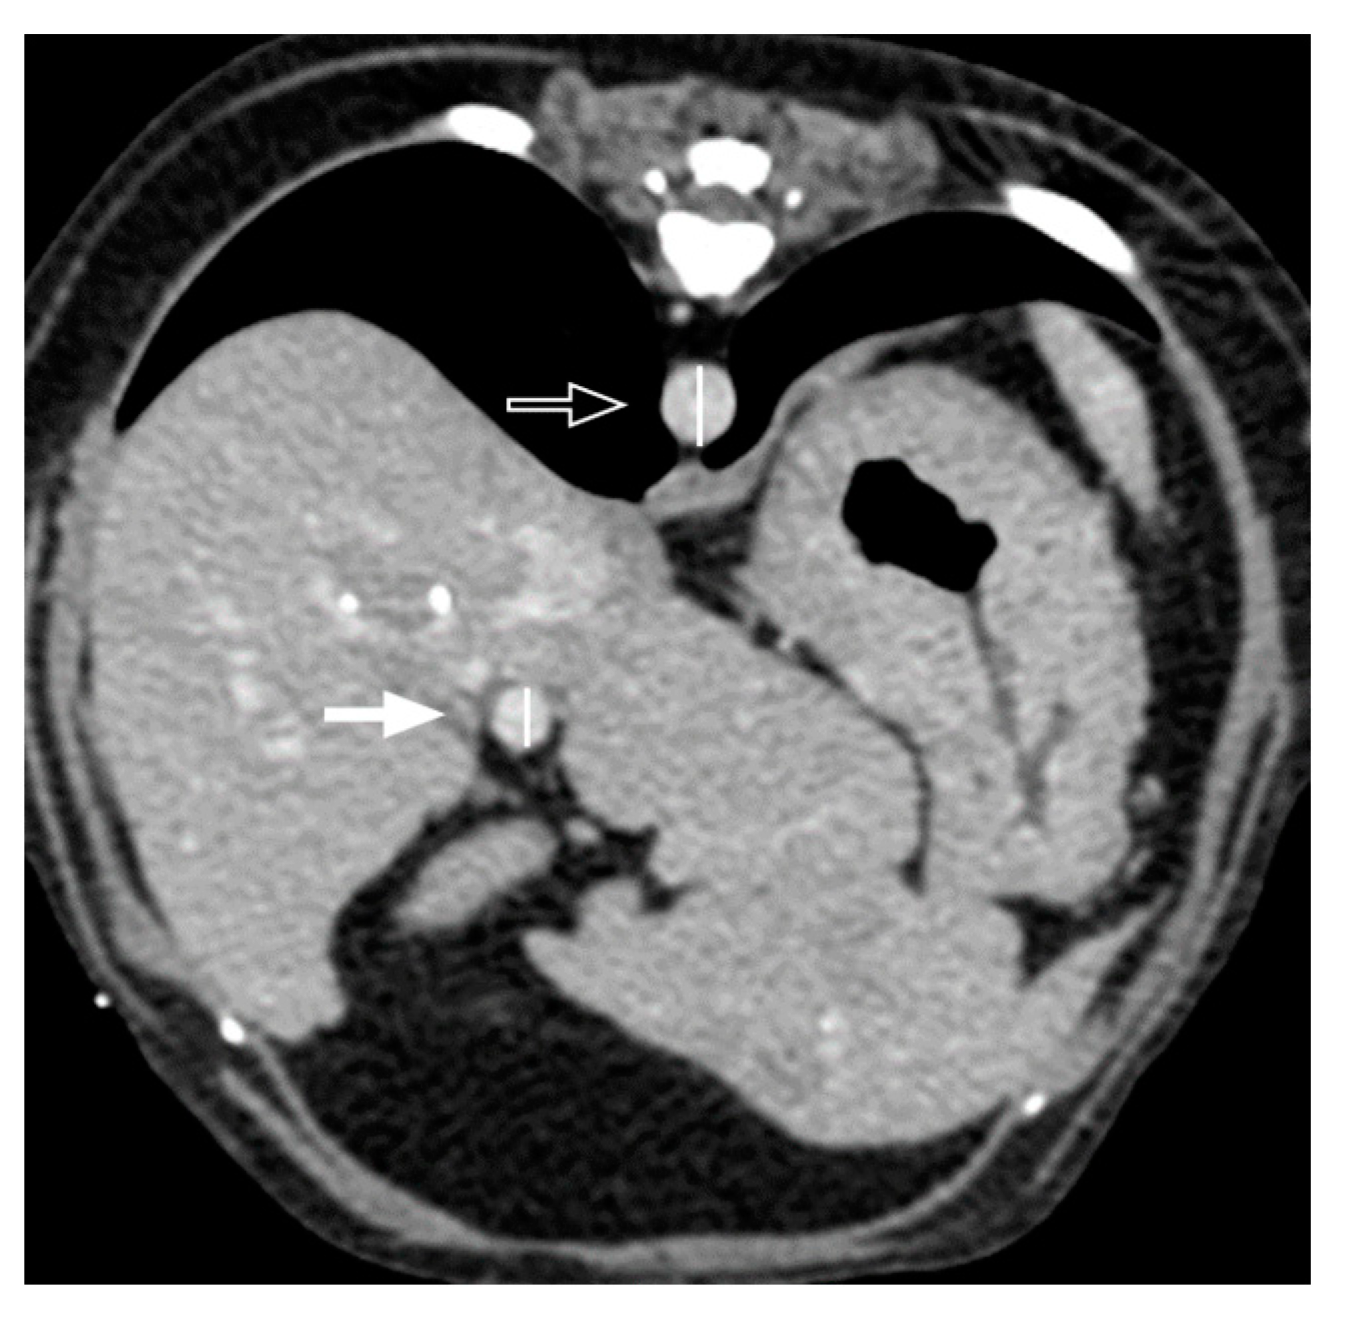

3.2. Qualitative Computed Tomographic Features

- Roncalli, M.; Roz, E.; Coggi, G.; Di Rocco, M.G.; Bossi, P.; Minola, E.; Gambacorta, M.; Borzio, M. The Vascular Profile of Regenerative and Dysplastic Nodules of the Cirrhotic Liver: Implications for Diagnosis and Classification. Hepatology 1999, 30, 1174–1178. [Google Scholar] [CrossRef]

- Brancatelli, G.; Federle, M.P.; Ambrosini, R.; Lagalla, R.; Carriero, A.; Midiri, M.; Vilgrain, V. Cirrhosis: CT and MR Imaging Evaluation. Eur. J. Radiol. 2007, 61, 57–69. [Google Scholar] [CrossRef]

- Ohtomo, K.; Baron, R.L.; Dodd, G.D.; Federle, M.P.; Miller, W.J.; Campbell, W.L.; Confer, S.R.; Weber, K.M. Confluent Hepatic Fibrosis in Advanced Cirrhosis: Appearance at CT. Radiology 1993, 188, 31–35. [Google Scholar] [CrossRef]